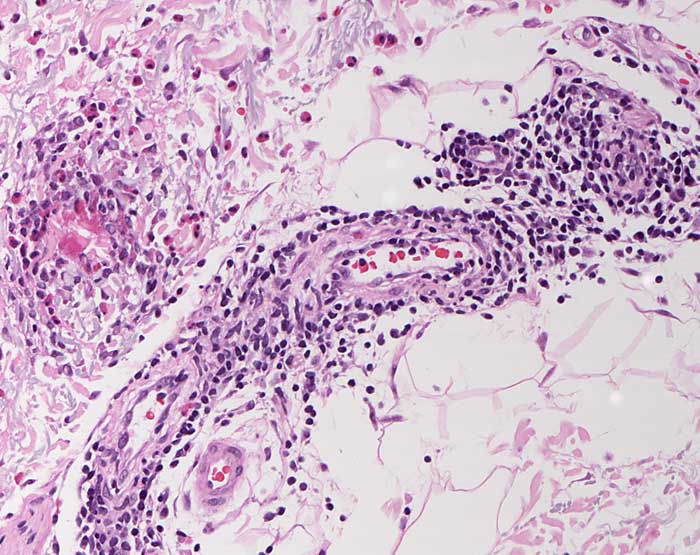

Arthropodenreaktion: Flammenfigur

Entzündung / Reparatur

Haut, obere Extremität

Bis in die Subkutis reichendes eosinophilenreiches perivaskuläres und interstitielles Infiltrat. Einzelne Plasmazellen. Links im Bild eine Flammenfigur bestehend aus zerfallenden eosinophilen Granulozyten, die um degenerierte Kollagenfasern angeordnet sind.

Stark juckende papulovesikulöse Läsionen am Unterarm.

Histologie

200